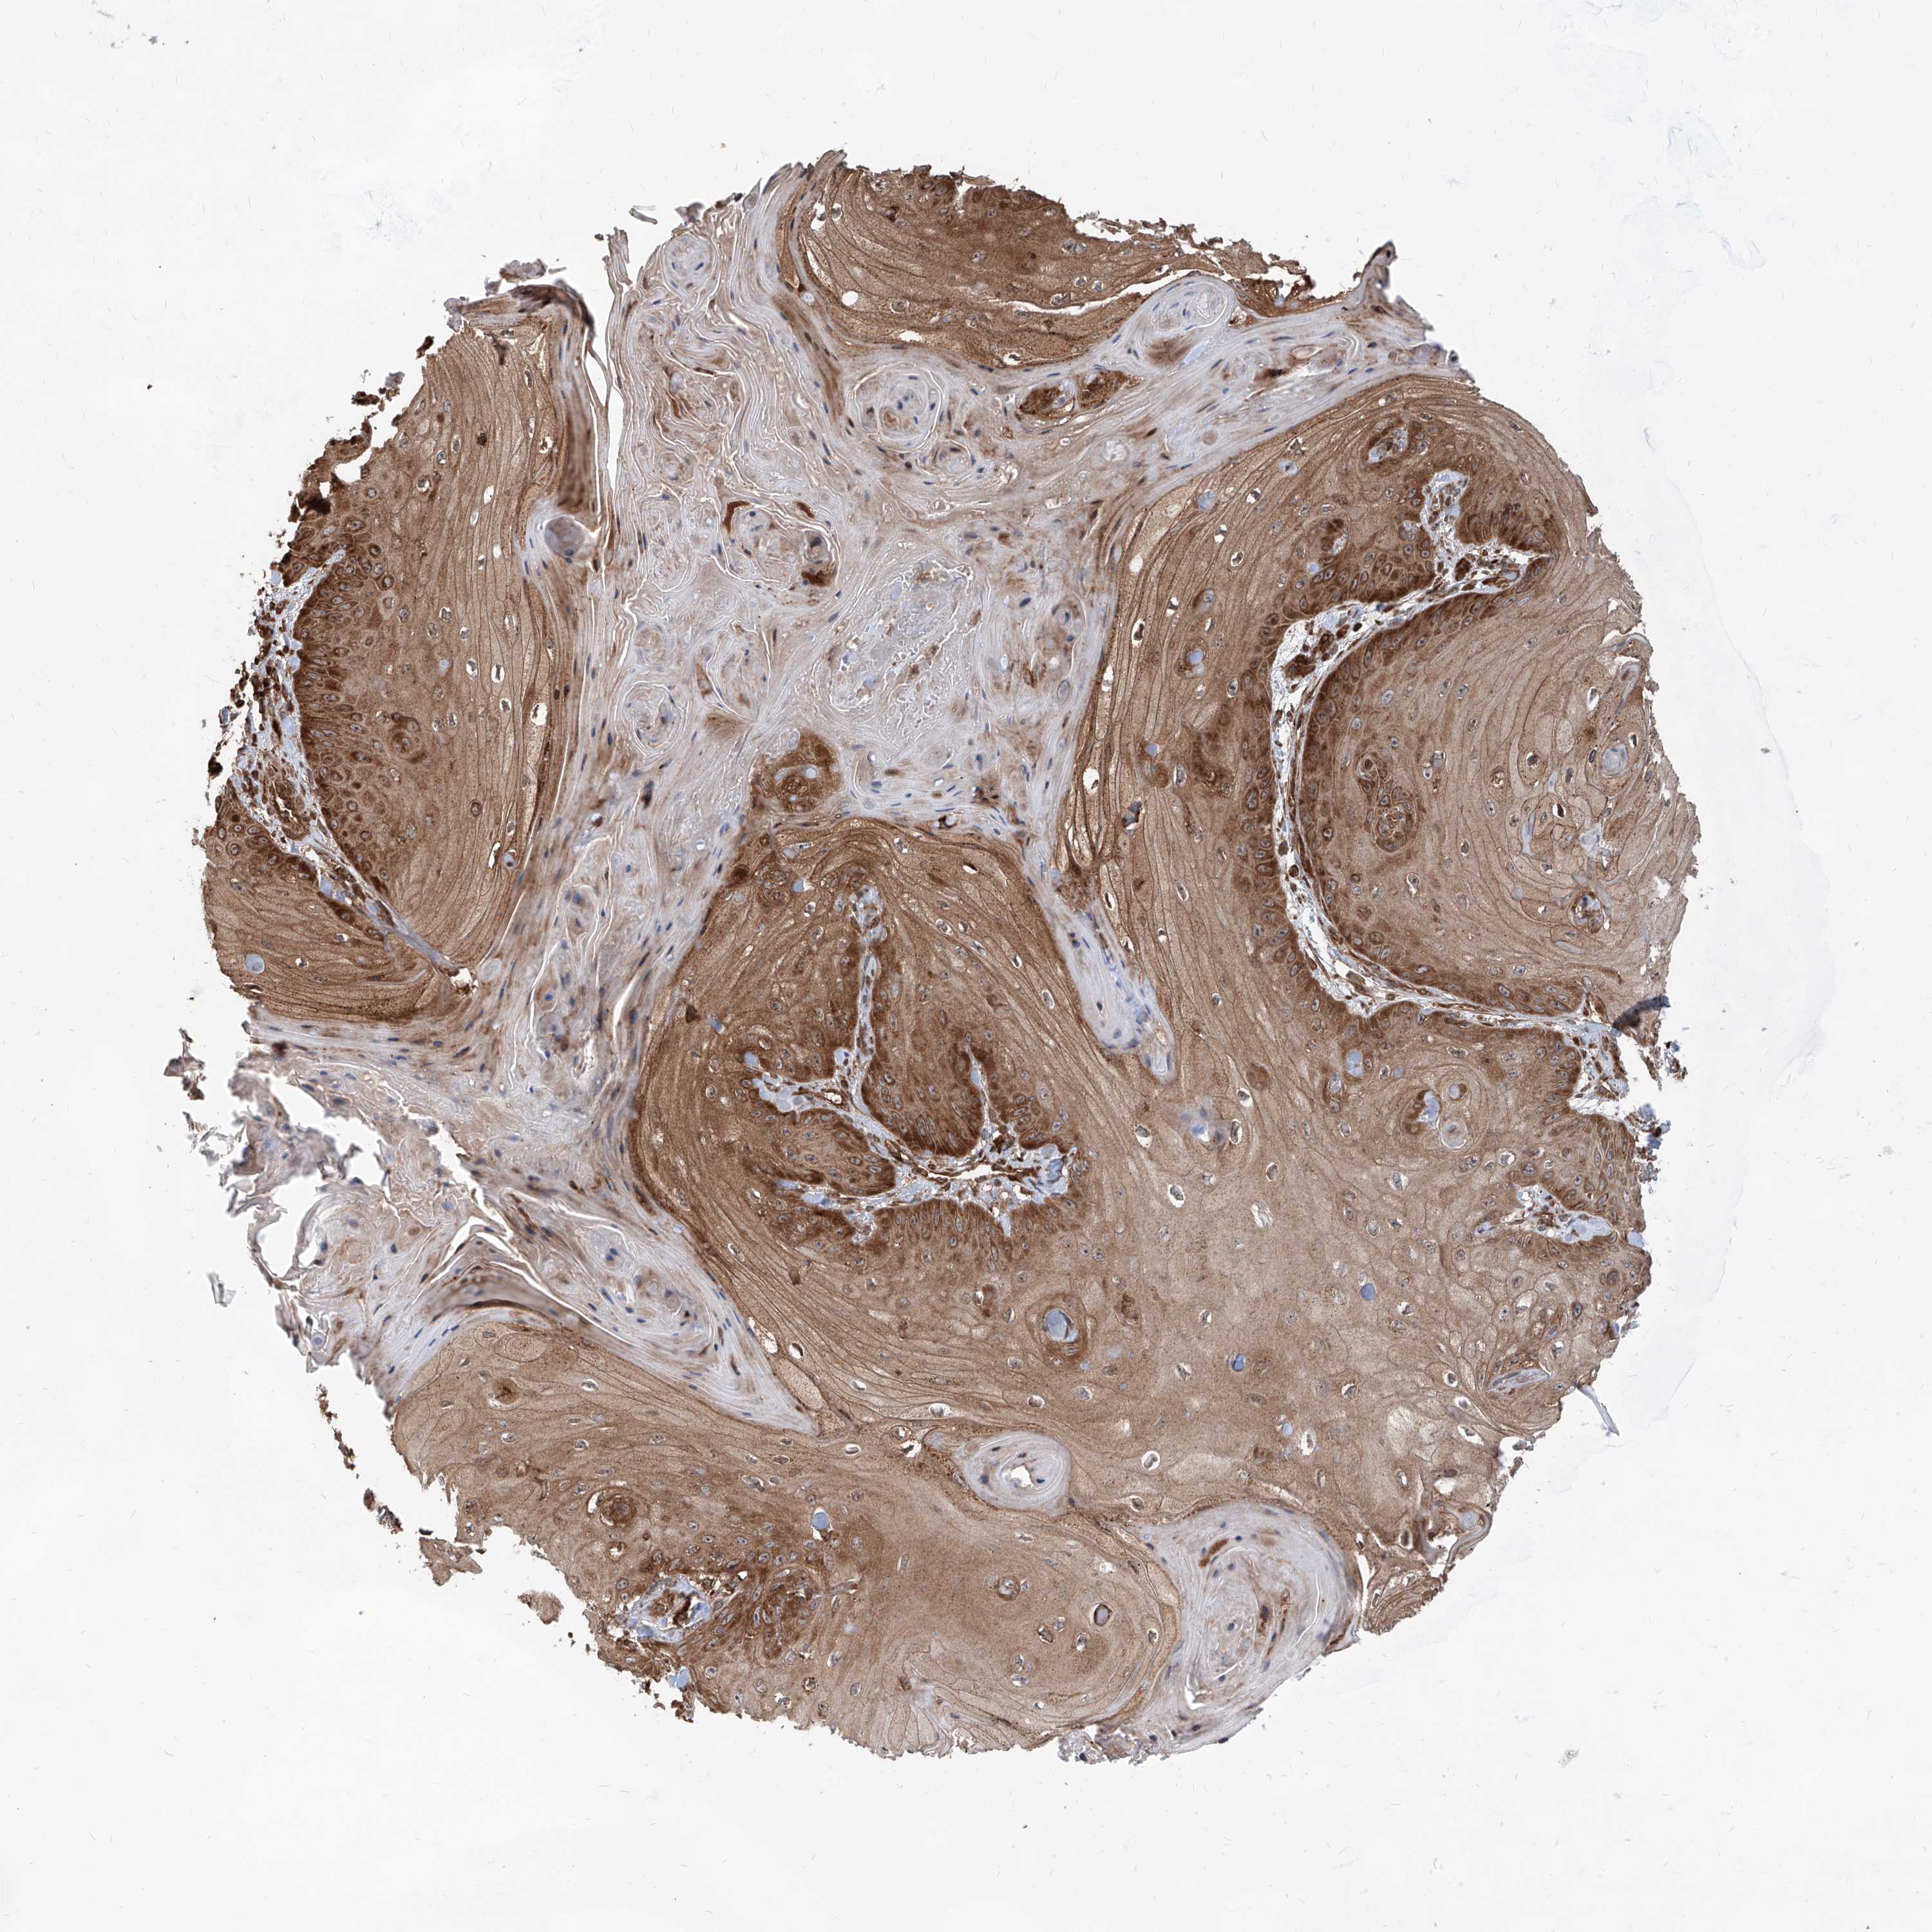

Basal cell and squamous cell cancer

SKIN CANCER - Protein expressioni

A mouse-over function shows sample information and annotation data. Click on an image to view it in a full screen mode. Samples can be filtered based on level of antibody staining by selecting one or several of the following categories: high, medium, low and not detected. The assay and annotation is described here.

Each image is clickable and will lead to virtual microscopy that enables deeper exploration of all samples and also displays staining intensity scores, fraction scores and subcellular localization as well as patient and tissue information for each sample.

Antibody HPA031572

Antibody HPA031573

Basal cell carcinoma